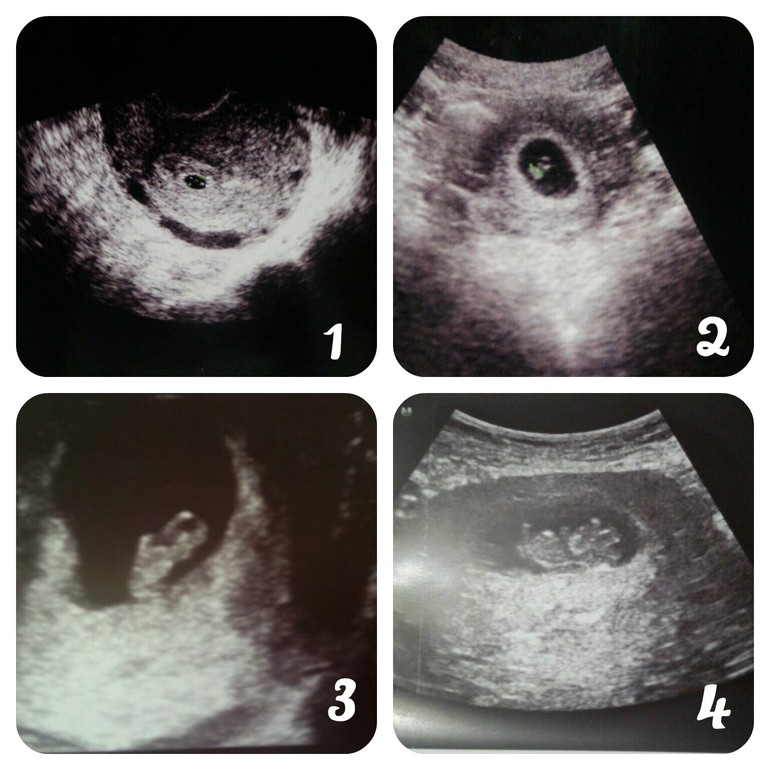

Ну и наши фоточки и экспериментальный график БТ 😁

Вот так мы растем: